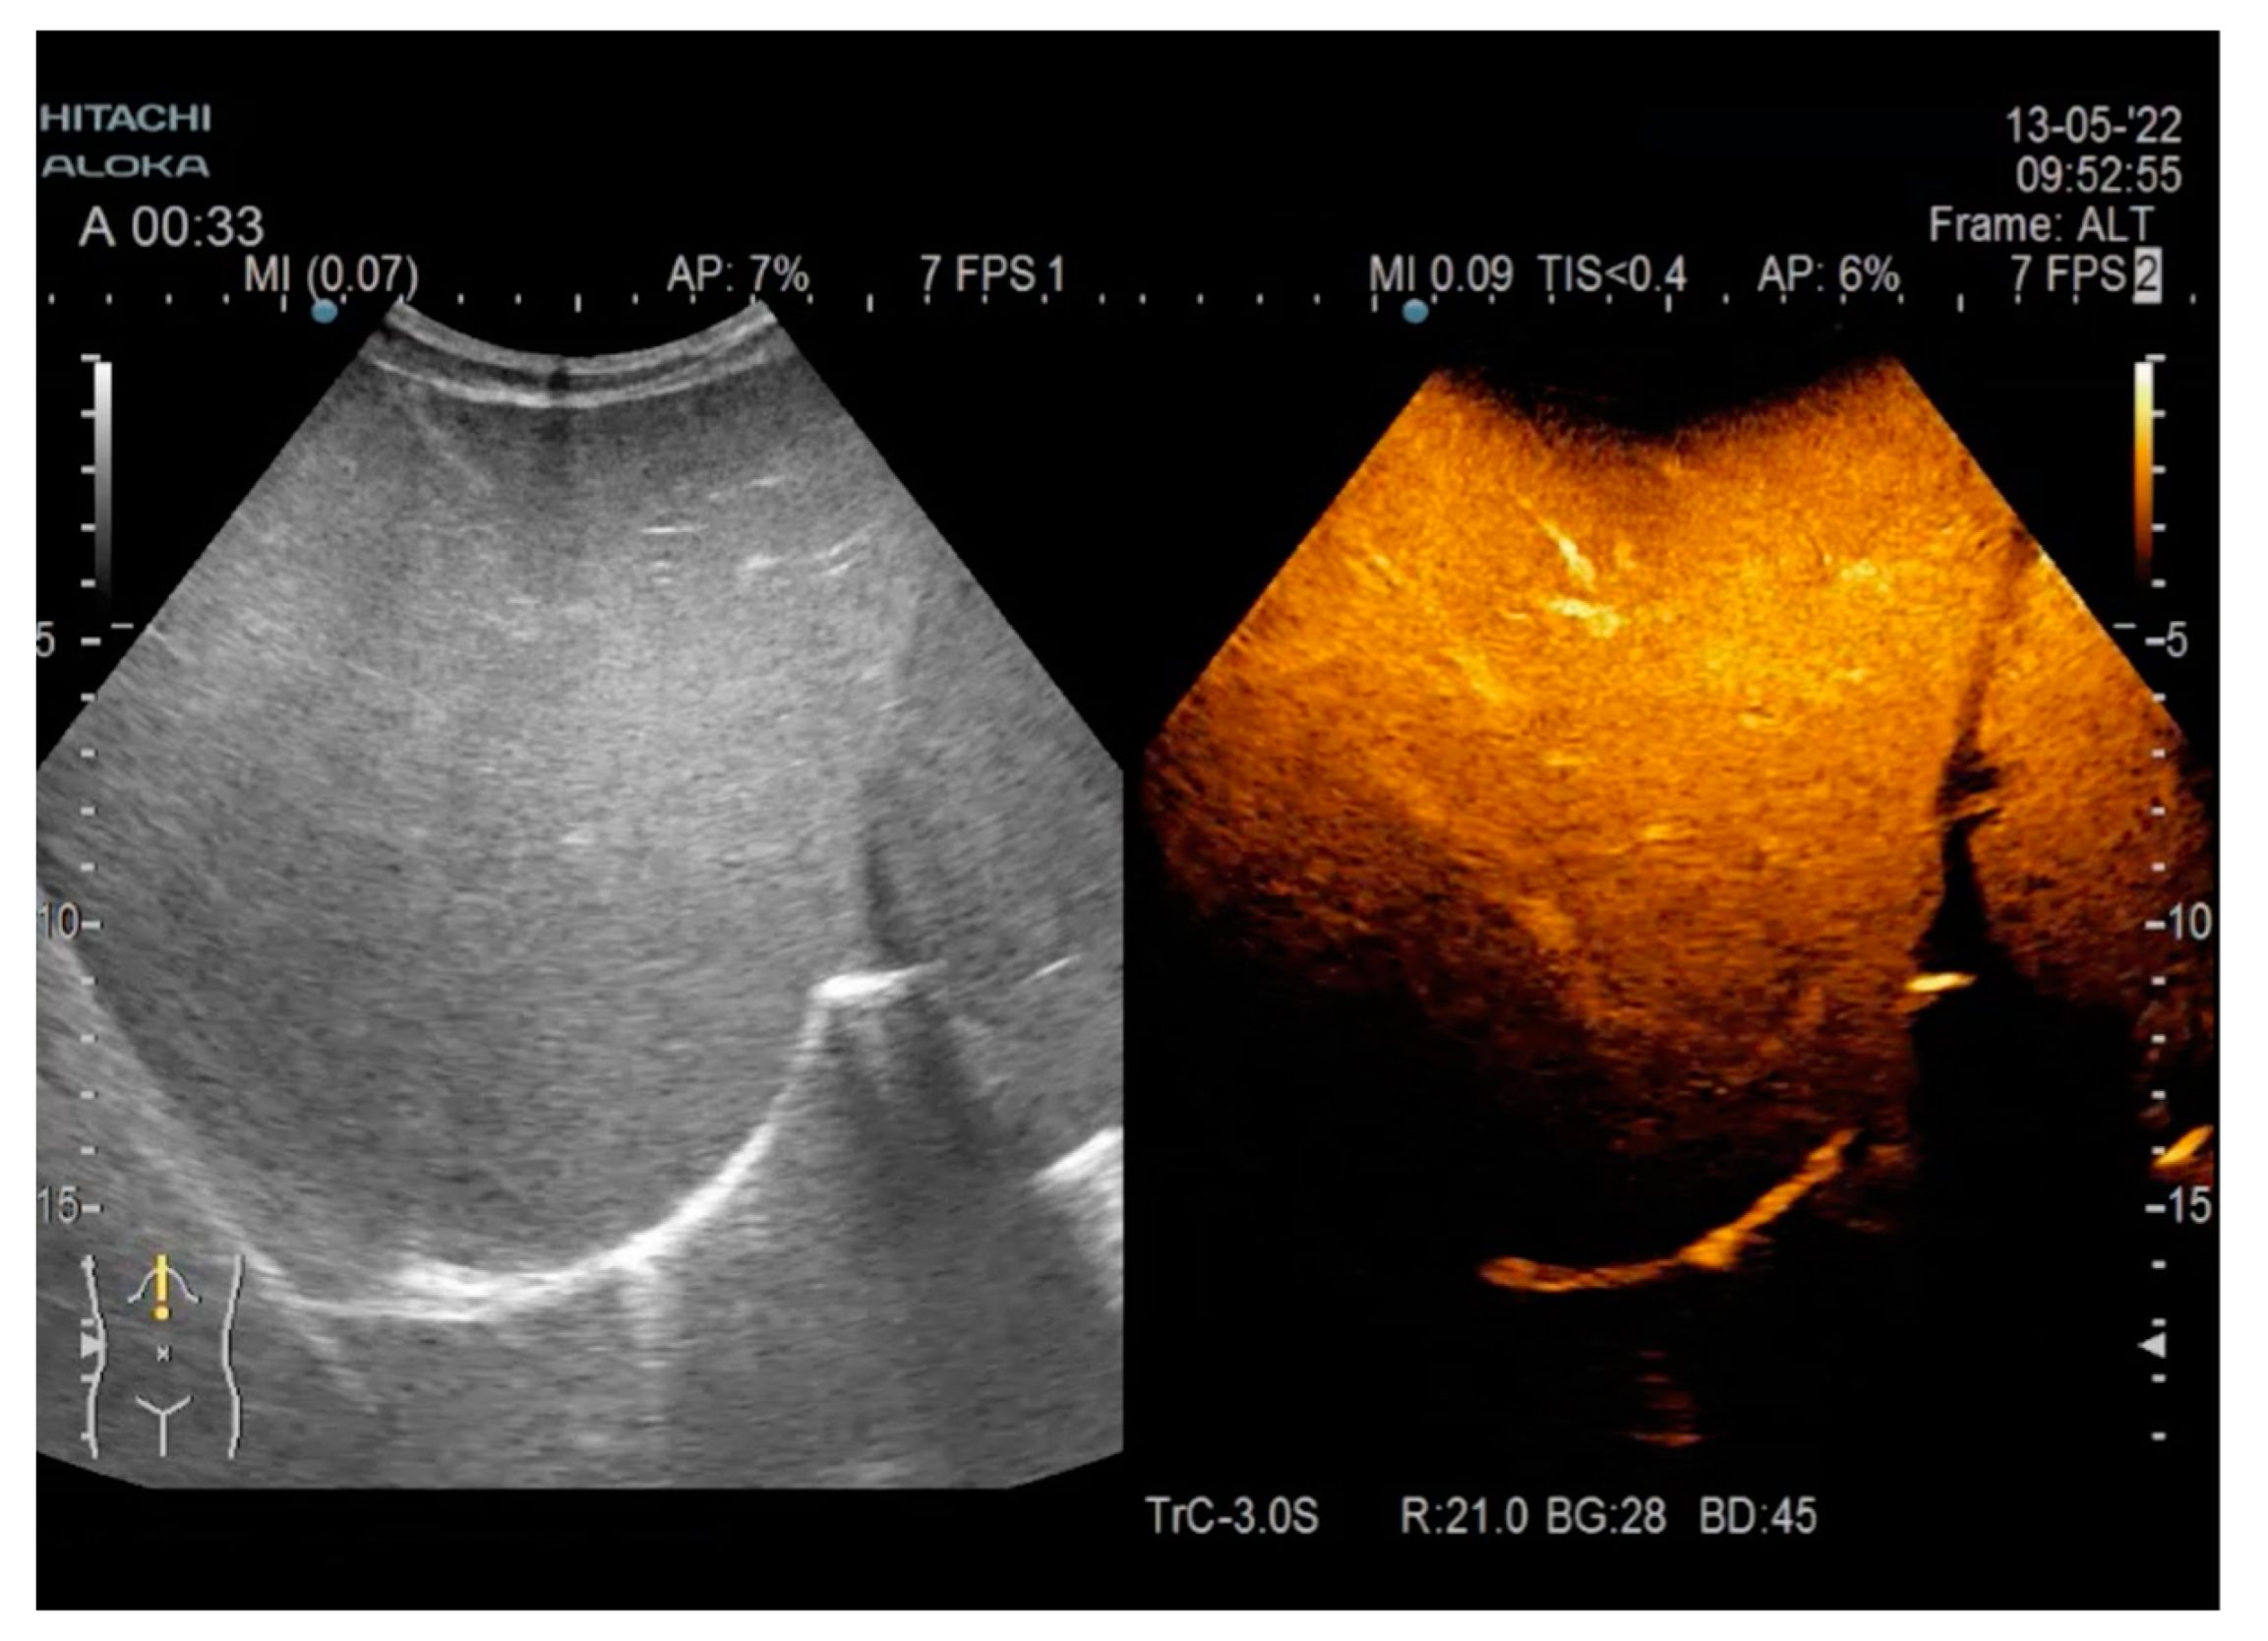

2. Case Report